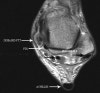

MRI : 후경골근 장애(Posterior tibial tendon dysfunction, PTTD)